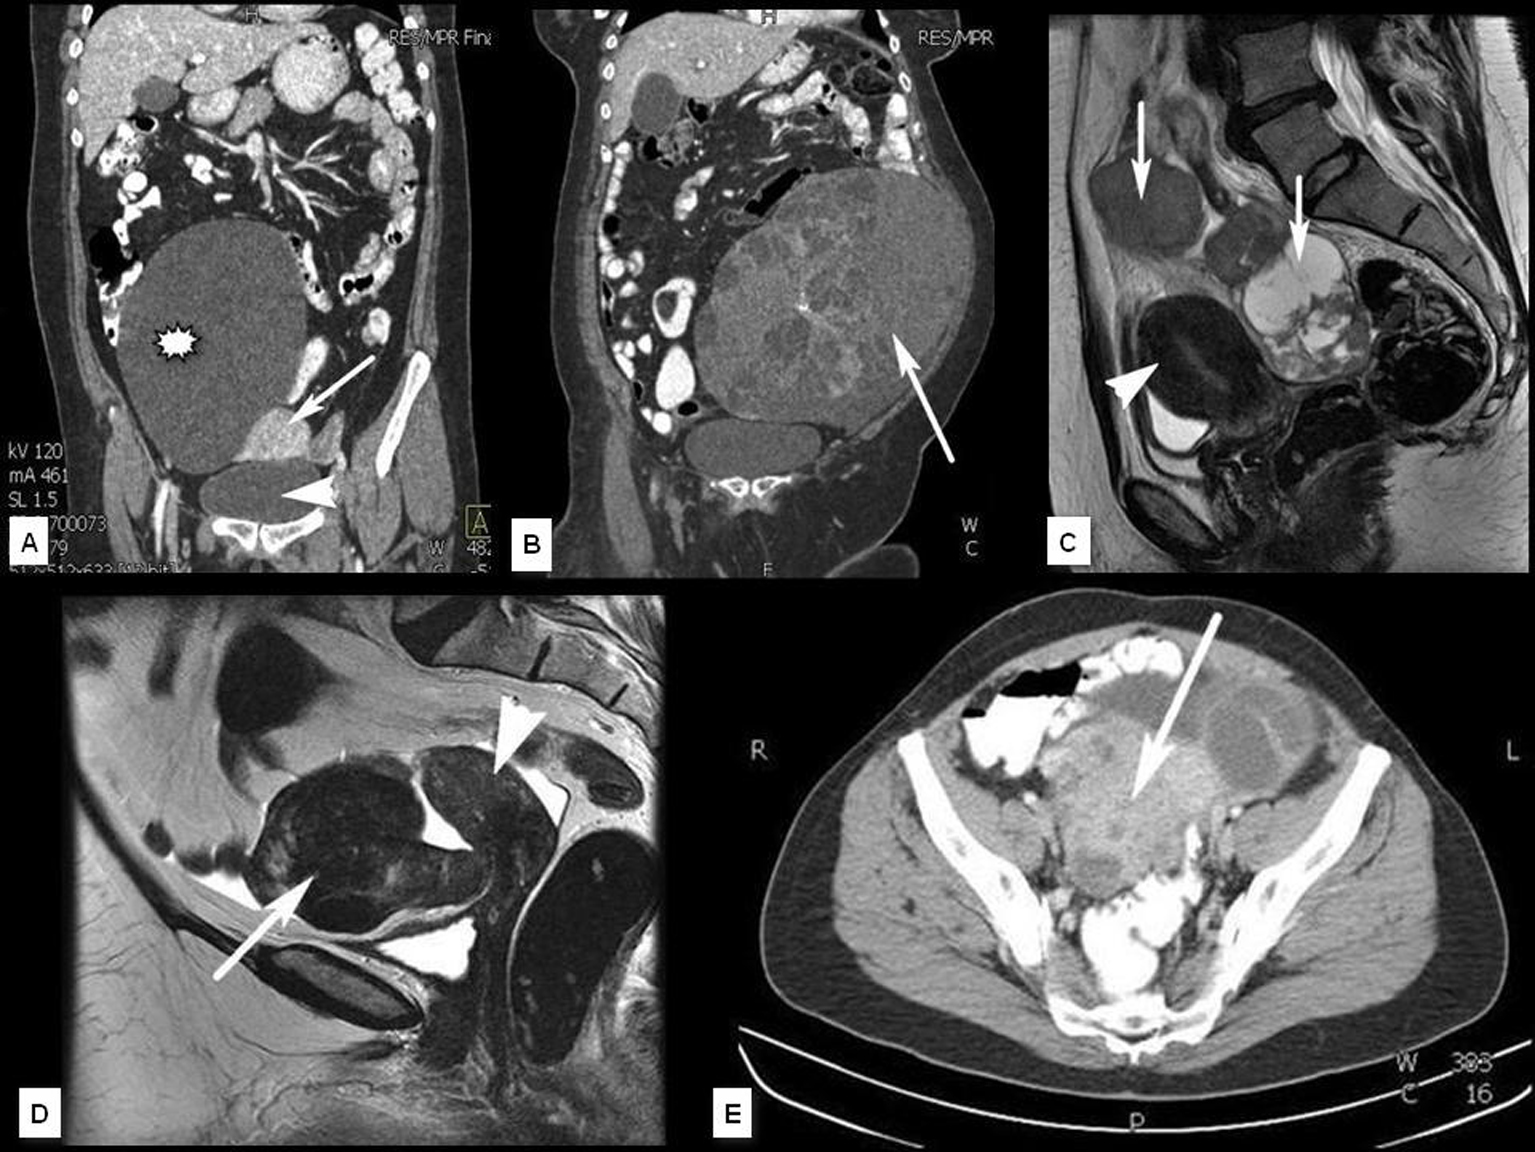

En el contexto del abordaje multidisciplinar para el diagnóstico y tratamiento del cáncer de ovario, la aportación del radiólogo incluye cuatro puntos fundamentales que son: identificación de la lesión, caracterización, estudio de extensión y valoración evolutiva. En el presente trabajo se describen los hallazgos y claves diagnósticas en TCMD (Tomografía Computarizada multidetector) y RM (Resonancia Magnética), la aportación e indicación de otras tecnologías como el PET (Tomografía por Emisión de Positrones) y se esbozan las técnicas emergentes basadas en imagen funcional (estudios dinámicos con contraste en RM y estudios de difusión por RM).Descargas